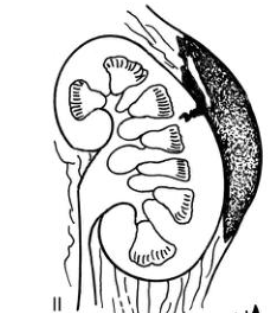

Trzeci stopień uszkodzenia nerki

Rozdarcie miąższu >1cm, bez uszkodzenia dróg moczowych

Czwarty stopień uszkodzenia nerki

Duże rozdarcie miąższu + uszkodzenie dróg moczowych,

Powiększający się krwiak

Izolowane uszkodzenie tętnicy/żyły nerkowej

Piąty stopień uszkodzenia nerki

Oderwanie szypuły naczyniowej, rozkawałkowanie nerki